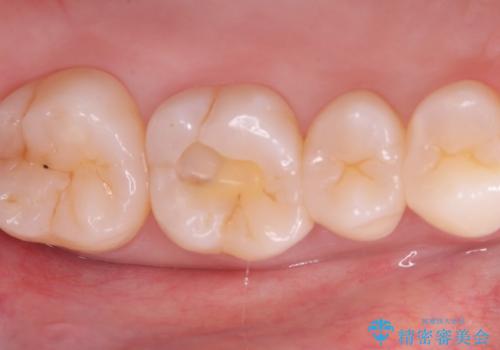

- 主訴:奥歯の噛む面が虫歯になっている。プラスチックの材料で治療可能と言われたが、劣化してまた虫歯になるのが怖いのでセラミックの詰め物にしたい。

咬合面にう蝕があり、CR修復・各種インレーの特徴を説明し、審美性・適合性の良いセラミックインレーでのやり替えとなりました。

咬合面のみのう蝕の場合CR(コンポジットレジン)修復を行うことが多いですが、CRは経年劣化しやすく二次う蝕の可能性を帯びています。それに比べセラミックは着色や収縮が少なく、経年劣化しにくい材料のため、今回はセラミックインレーでの治療となりました。